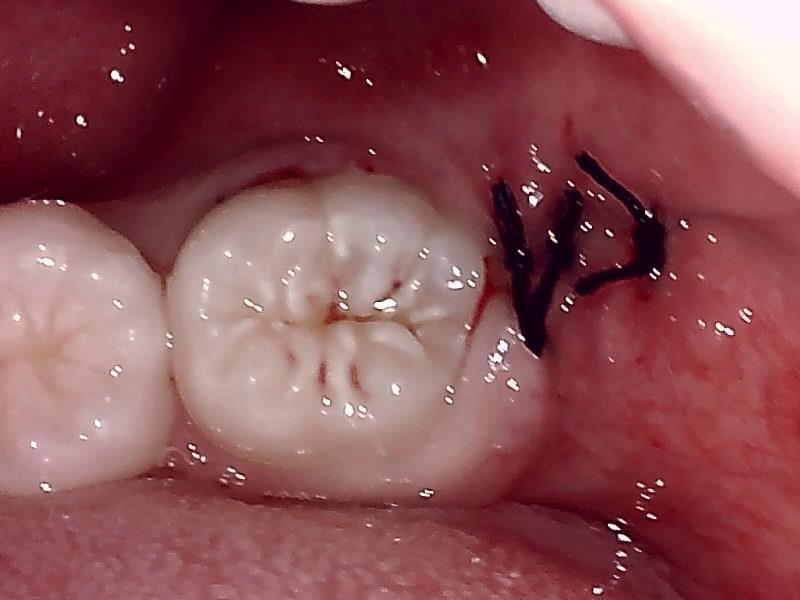

抜歯窩

縫合